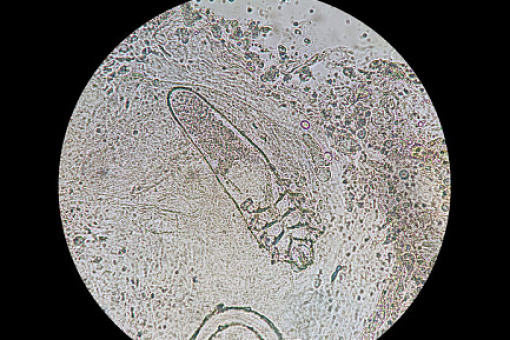

Obecnie nie ma standardu diagnostycznego demodekozy ocznej. Rozpoznanie ustala się na podstawie wywiadu, badania w lampie szczelinowej i potwierdzenia infestacji w badaniu mikroskopowym. Najpowszechniej stosowaną metodą diagnostyki jest badanie mikroskopowe epilowanych rzęs.